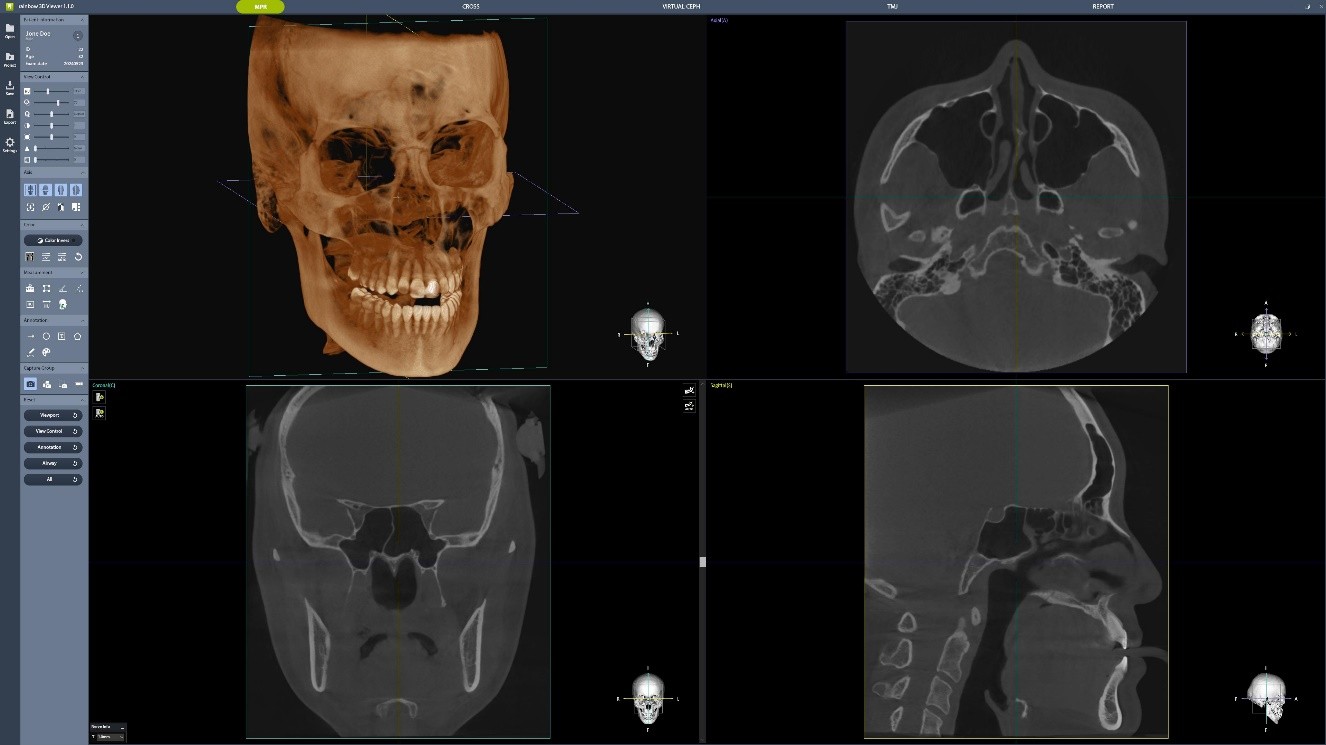

Câmp de Vizualizare Extins

Dentium Rainbow™ CT oferă un câmp de vizualizare extins de 16×18 cm, ideal pentru diagnosticul complet, de la planificarea implantului până la ortodonție. Funcția de suprapunere a imaginilor (Stitching) permite captarea detaliată a zonelor mandibulare și maxilare, generând imagini clare și precise, esențiale pentru intervențiile chirurgicale maxilo-faciale și diagnosticul ortodontic.

Stitching 16×18

Prin funcția de suprapunere a imaginilor (Stitching), se pot diagnostica zonele care nu ar putea fi vizualizate cu o imagine CT obișnuită, prin captarea imaginilor din zonele mandibulare și maxilare. Imaginile obținute sunt suprapuse pentru a genera o imagine mai largă și mai clară. Acest protocol este optimizat pentru intervenții chirurgicale maxilo-faciale și diagnostic ortodontic.